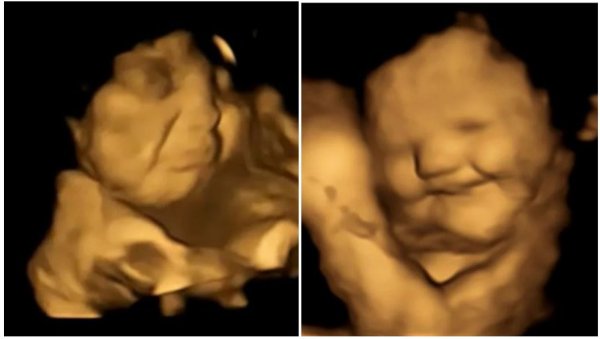

Da bi ispitali da li fetusi mogu da razlikuju različite ukuse, tim je ultrazvukom snimao 70 trudnica između 18 i 40 godina starosti, koje su bile podeljene u dve grupe. Trudnice u jednoj grupi su uzimale kapsulu sa keljom u prahu 20 minuta pre ultrazvuka, a one u drugoj grupi su dobijale kapsulu sa šargarepom u prahu. Sve trudnice su u periodu trudnoće imale sličnu ishranu i unos povrća. Sve žene u studiji nisu jele ništa sat vremena pre obavljanja ultrazvuka.

Foto: FETAP Study/Fetal and Neonatal Research Lab/Durham University

Tim naučnika je nakon pregleda obavljao analizu svakog snimljenog kadra i posmatrao izraze lica fetusa, uključujući i kombinacije grimasa koje su izgledale kao plač ili smejanje. Napravljeno je više od 180 ultrazvučnih snimaka na 99 fetusa, koji su skenirani u 32. i 36. nedelji trudnoće.

Plačni izrazi lica bili su dva puta češći kada su majke konzumirale kapsule sa keljom u poređenju sa fetusima čije su majke uzimale kapsule sa šargarepom ili nisu uopšte uzimale kapsule. U slučaju kapsula sa ukusom šargarepe, lica nerođenih beba su često dobijala izraz osmehivanja.